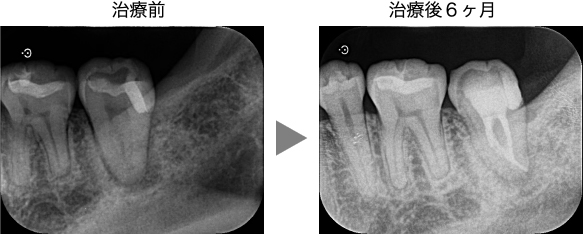

レントゲン写真にて、根の先の黒い影(骨の吸収像)の縮小傾向が認められました。

症状もなく、フィステルも治療後すぐに消失したとのことでした。

わずかにまだ黒い影が残っているため、さらに追加で6ヶ月、術後12ヶ月まで経過をみることになりました。